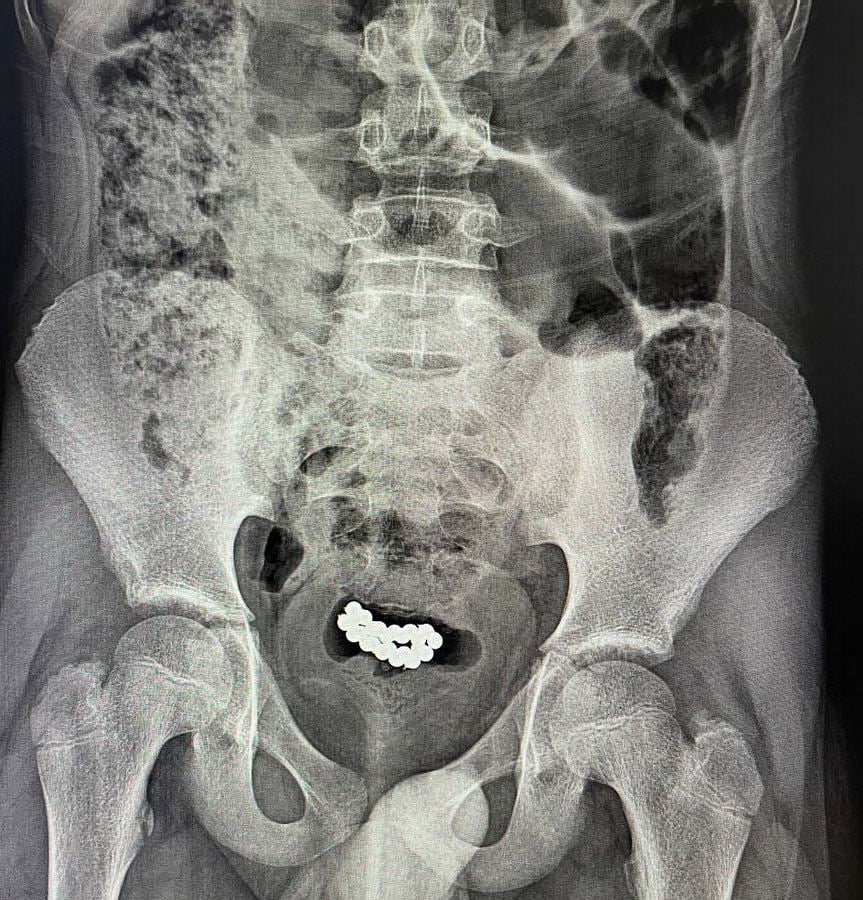

За останні три місяці в нашому закладі успішно було прооперовано два ідентичні випадки евакуації магнітних кульок з сечового міхура хлопчиків віком 10-15 років. В обох випадках було виконано цистотомію міні-лапаротомним доступом з подальшим вилученням 62 та 24 магнітних кульок.

Післяопераційний період у цих пацієнтів пройшов без ускладнень, і вони були виписані додому у задовільному стані», – йдеться у дописі.